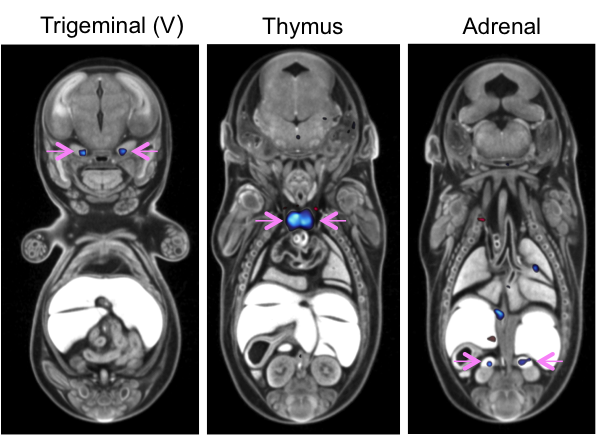

Chromobox 4 is in the polycomb protein family that are key regulators of transcription and is reported to be upregulated in lung bud formation and required for thymus development. Cbx4 mutants showed complete preweaning lethality but were viable at E12.5 and E15.5 with no obvious gross morphological change. Micro-CT analysis at E15.5 confirmed that Cbx4tm1.1/tm1.1mutants had statistically smaller thymus and also revealed smaller adrenal glands and trigeminal ganglia compared to Cbx4+/+ wildtype embryos.

Automated MRI analysis of E15.5 Cbx4tm1.1/tm1.1 mutants viewed in coronal section revealed that mutant embryos had bilateral smaller trigeminal ganglia, thymus, and adrenal glands compared to Cbx4+/+ wildtype embryos as indicated by blue colour and highlighted by pink arrows (False Discovery Rate (FDR) threshold of 5%).